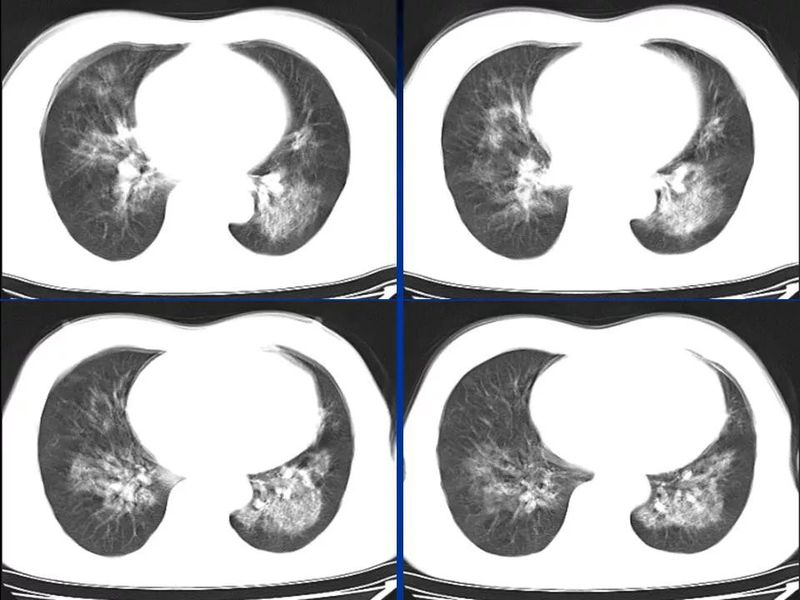

主任提醒:这个病很容易误诊为肺炎!